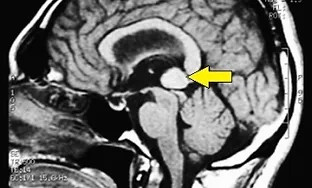

Scénarios diagnostiques récurrents observés au sein du Masticationpedia Network (et non des rapports de cas isolés). Tous les centres du Network habilités utilisent des technologies et des méthodologies neurophysiologiques permettant des diagnostics précoces et précis de pathologies imitant des symptomatologies odontologiques, telles que les Troubles Temporo-Mandibulaires et les Douleurs Orofaciales, qui peuvent parfois masquer des atteintes organiques neurologiques et systémiques. En outre, le savoir-faire acquis permet un contrôle et une finalisation des traitements orthodontiques, prothétiques et implantoprothétiques optimisés selon les réponses neurophysiologiques trigéminales, et non uniquement sur des paramètres de forme et d’esthétique.

Troubles temporo-mandibulaires